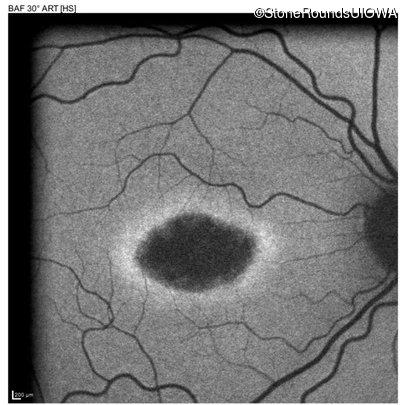

Blue Autofluorescence - Right - 20/32 sc

Exemplar